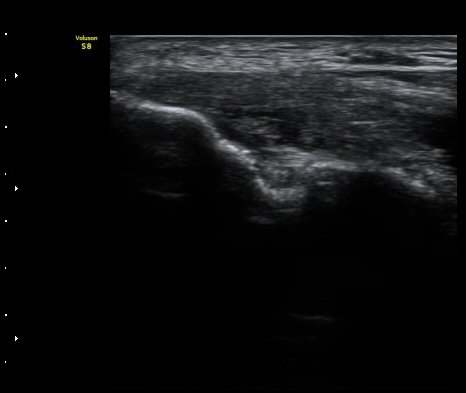

ÃÊÀ½ÆÄ °Ë»ç

³»»ó°ú¿¡¼­ ¼Õ¸ñ±¼°î°Ç Á¾´Ü¸é°Ë»ç»ó ³»¤µ¾Æ°ú ÇÇÁú°ñÀÇ ºÒ±ÔÄ¢º¯È­¿Í ÈûÁÙ³» ¿¬°á¼º

¼Ò½Ç ¹× Àü¹ÝÀûÀÎ Àú¿¡ÄÚ ºÎÁ¾ÀÌ °üÂûµÈ´Ù(±×¸² 1, 2, 3). ±¼°î°Ç ÀϺδ Á¤»óÀûÀÎ °í¿¡ÄÚ